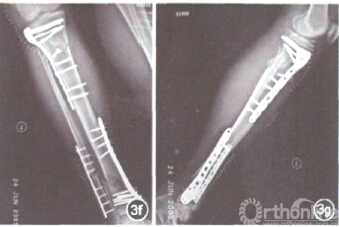

图1下肢骨折牵引复位器各部分组件。支撑调节框架为三角形框架结构,具自角度可调节装置,通过角度调整以适应术中下肢的屈髋屈膝位摆放。牵引复位弓通过丝杠传动式机械牵拉装置的牵引,可以对骨折多向牵引复位。支撑垫可支撑和限定患者下肢 图2患者胫骨干42-B2型骨折。应用下肢骨折牵引复位器行胫骨骨折闭合复位、带锁髓内针内固定术(2a);胫腓骨骨折术后正、侧位X线片(2b);胫腓骨骨折术后正、侧位X线片(2c) 图3患者胫骨近端41-C1.3型骨折合并同侧胫骨远端43-A3型骨折。应用下肢骨折牵引复位器行胫骨近、远骨折有限切开复位、锁定钢板经皮插入内固定术(3a);骨折术前正、侧位X线片(3b,3c);术中在复位器对骨折的牵引复位辅助下,应用大巾钳经皮夹持骨折复位,复位器的设计为其他复位手段留有足够操作空问,透X线金属材质以利于术中应用C臂机透视、监测骨折复位情况及内固定物位置(3d,3e);骨折术后正、侧位X线片(3f,3g)